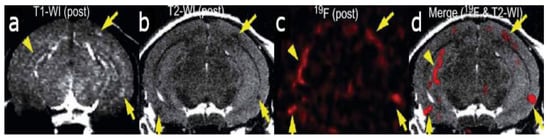

Figure 1.

In vivo detection of amyloid plaques (indicated by arrowheads and arrows) in the brain of a Tg2576 mouse after injection with (E,E)-1-fluoro-2,5-bis(3-hydroxycarbonyl-4-hydroxy)styryl-benzene (FSB) [14]. (a) T1-weighted 1H imaging of the mouse brain. (b) T2-weighted image of the same slice indicating the position of the amyloid-beta plaques. (c) 19F MRI image of the mouse brain after FSB injection. (d) 19F-FSB image overlaid on top of the high-resolution T2-weighted 1H image. Images are reprinted with permission from the publisher [14].